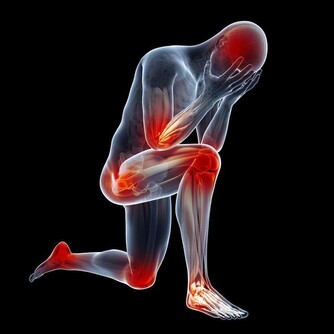

是由於變老的生理變化和病理變化,使患病的機率升高,衰老本身就是許多疾病的風險因素。

所以,變老不僅包括機體生理上的衰退,也包括在這個過程中發生的病理變化。